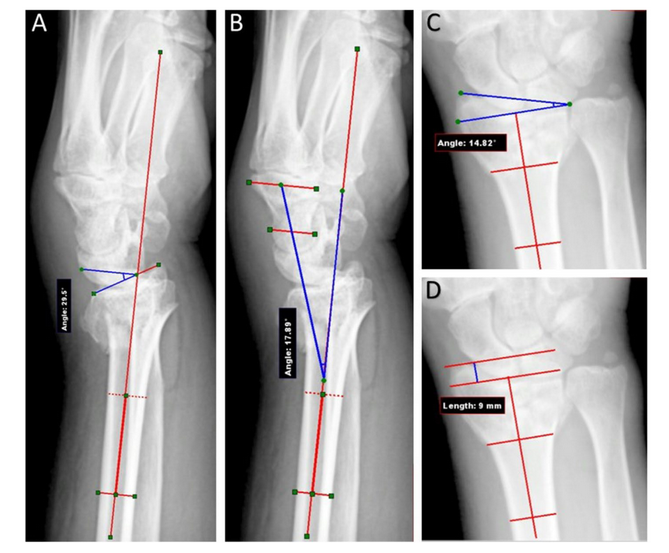

A-D术前放射学参数测量:手掌倾斜度(A)、手腕对中度(B)、径向倾斜度(C)、半径高度(D)

方法:对两组患者术前、术后即刻及术后6周的影像学及临床指标进行评价。术后12周对患者进行临床随访。采用患者腕部评分法(PRWE)、梅奥腕部评分法(Mayo Wrist score)和臂、肩、手快速残疾量表(DASH)评估患者的临床和功能状态。

结果:B组术后即刻(P = 0.007)和术后6周随访时(P=0.013)掌倾角均较a组改善(P=0.001和< 0.001),桡骨高度和桡骨倾斜度均较a组改善(P=0.001)。手术后12周,两组研究的任何临床结果(活动范围、握力、PRWE、Mayo和DASH评分)均无差异。